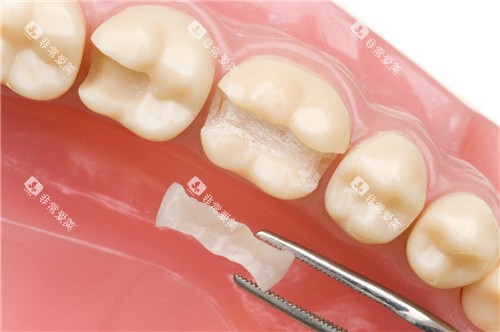

牙齿贴面可以改善牙齿的颜色、形状和大小,让牙齿更加美观。

郴州第三人民医院口腔科常见的牙齿贴面有瓷贴面和树脂贴面。

树脂贴面价格较为便宜,每颗牙齿的收费在300 - 800元左右。

但它的耐磨性和美观度相对瓷贴面较差。

瓷贴面的结果更好,更加美观、耐用,每颗牙齿的收费在1500 - 3000元左右。